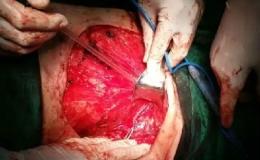

寿县中医院外科

目前我科在刘宏科主任带领下,全面开展微创技术,其中腹腔镜阑尾切除术(LA)是随着腹腔镜技术发展而兴起的一种新的手术方法。1983年Semm报道了首例经腹腔镜切除非急性炎症的阑尾,较腹腔镜胆囊切除术早4年,而腹腔镜下急性阑尾炎的阑尾切除术是1987年Semm首

双镜联合 填补寿县空白

近日,我院外科成功在全麻下为一位高龄女性患者成功实施腹腔镜联合胆道镜下胆囊切除+胆总管切开探查+T管引流术,填补了寿县手术技术空白。 患者系梗阻性黄疸入院,检查考虑胆管结石(泥沙型),经过周密的术前准备,手术小组决定采取腹腔镜联合胆道镜手术,